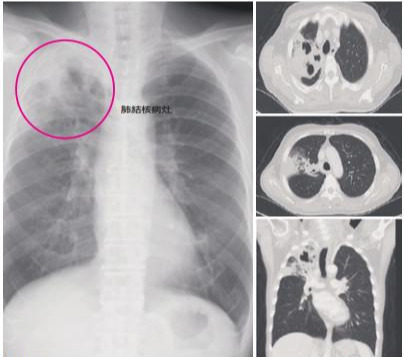

肺结核病人的CT

痰液结核菌抹片检查:若检验结果为阳性则表示痰液可能有结核菌,是诊断肺结核病是否具传染力的主要方法。但最后仍以痰液的培养结果,若又长出典型结核菌株,表示确定为结核菌感染。胸部X光或电脑断层:当怀疑有结核菌感染时,可用于确定病灶和侵犯的部位,但检验结果还是以痰液检查为最后诊断依据。